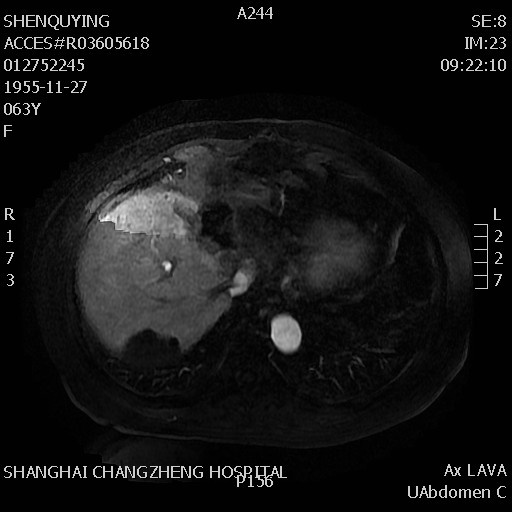

腹部MRI:

检查时间:2018年10月19日

影像图谱:T2

2018年10月18日基线扫描,腹部MRI提示:左肝切缘见一长径约5cm的类椭圆形复发灶,与胃壁及十二指肠降段关系密切,后腹膜见肿大淋巴结。胸部CT未见明显转移征象。

影像图谱:增强动脉期和延迟期